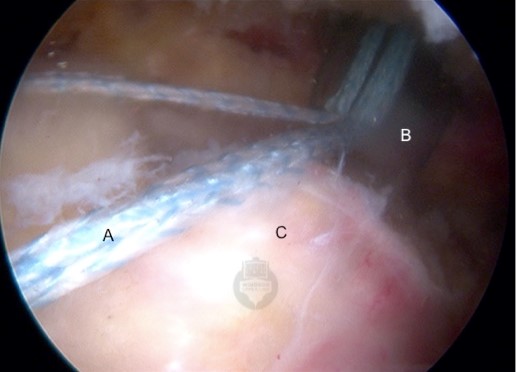

Tape Sutures (A) are passed through the tendon tissue (C) and brought

out of the shoulder through a plastic cannula (B) to be loaded onto an anchor